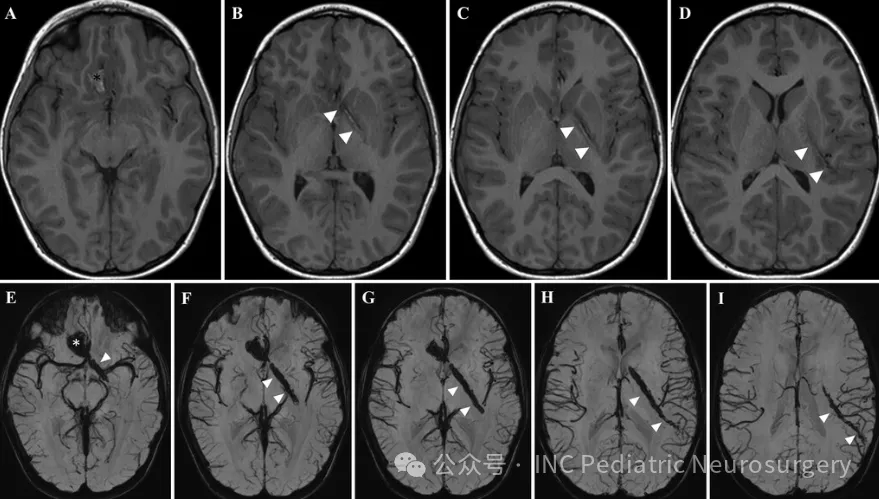

影像学检查发现

影像学检查显示:

右侧额叶脑实质出血灶向左顶叶延伸

出血路径经过胼胝体膝部、左侧苍白球、内囊前肢和左侧后部岛叶

合并右侧眶顶骨折及局灶性蛛网膜下腔出血

血管造影检查证实:

颈内动脉、基底动脉和椎动脉的颅内分支血流通畅

未见明显血管狭窄或颅内夹层形成

值得注意的是,铁杆穿透路径恰好避开大脑前动脉,勉强规避内囊后肢,最终止于对侧左侧颞上回。眼科检查显示视力正常,仅见轻微结膜下出血。